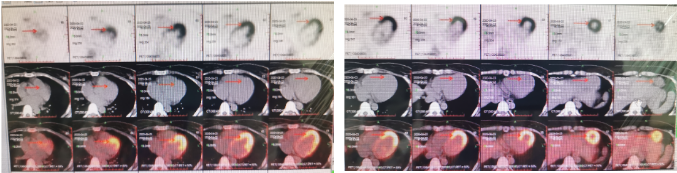

明确缺血证据PET/CT -hibernating myocardium

MRI 室壁瘤

2019-1 CTA 无严重钙化